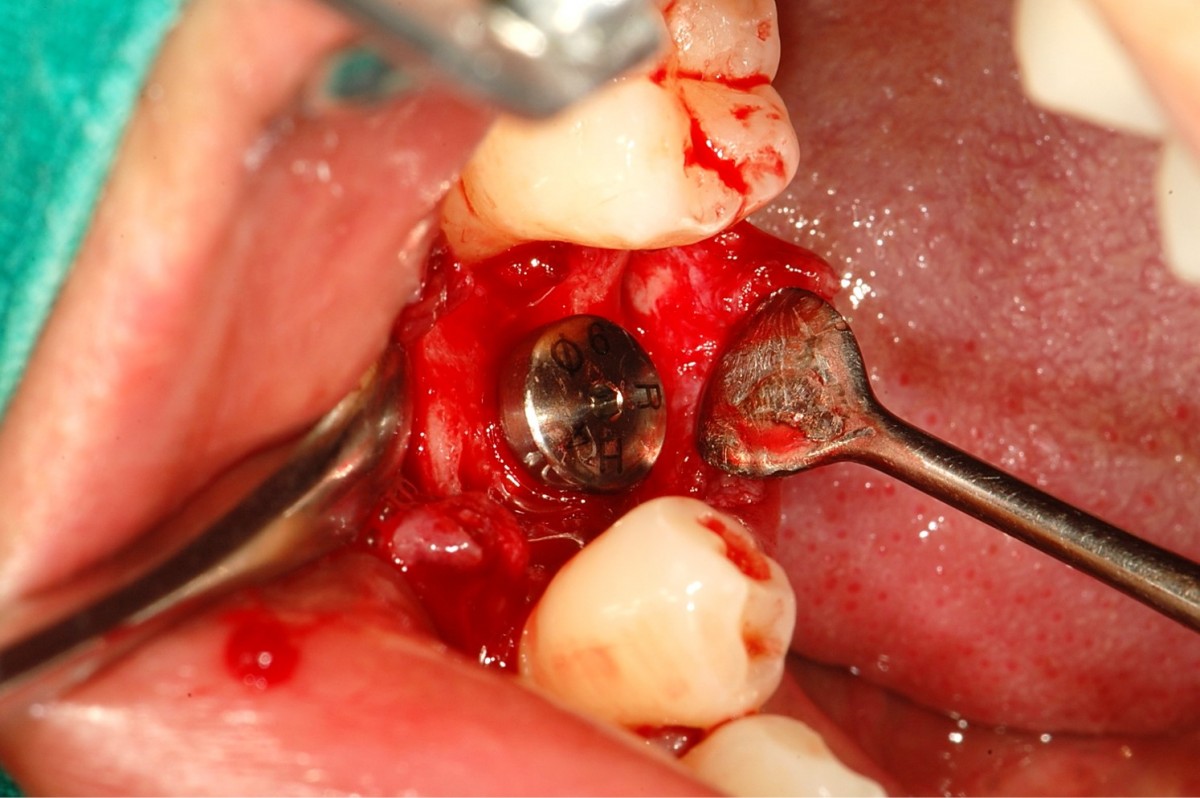

▲Radiograph after impant surgery.